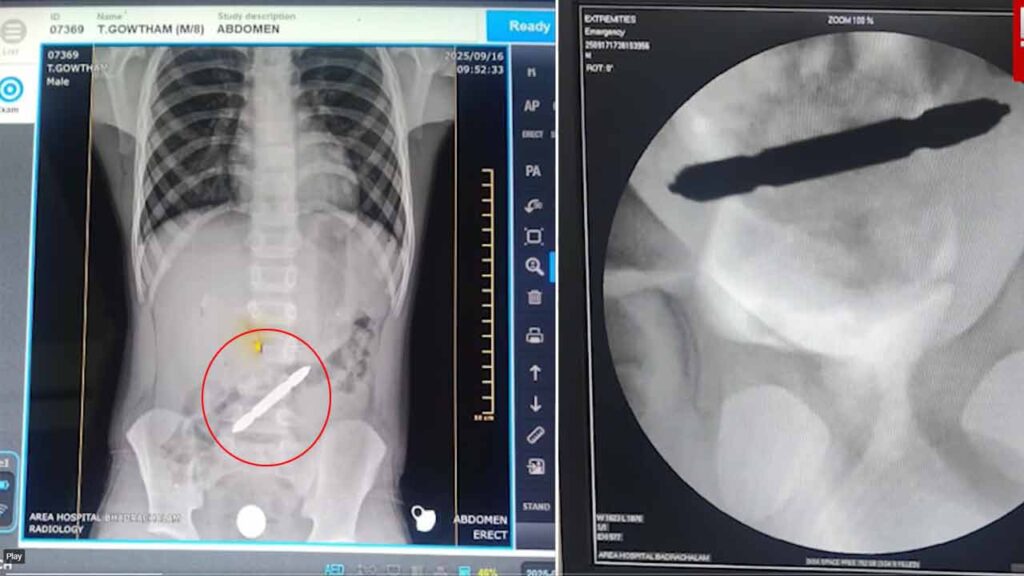

బాధిత బాలుడికి డాక్టర్లు ఎక్స్ రే( X Ray ) తీయగా.. పెద్ద పేగులో స్క్రూ డ్రైవర్ అడ్డంగా ఇరుక్కుపోయినట్లు గుర్తించారు. మొదట మలం ద్వారా బయటకు తీసుకొచ్చేందుకు యత్నించారు. కానీ సాయంత్రానికి బాలుడు తీవ్రమైన కడుపునొప్పితో బాధపడడం, ఆకస్మాత్తుగా వాంతులు కావడంతో వైద్యులు అప్రమత్తమయ్యారు.

ఏ మాత్రం ఆలస్యం చేయకుండా బాలుడిని ఆపరేషన్ థియేటర్కు తరలించారు. మూడు గంటల పాటు సర్జరీ నిర్వహించి స్క్రూ డ్రైవర్ను తొలగించారు. ఈ వస్తువు ఆరు సెంటిమీటర్లు ఉన్నట్లు వైద్యులు తెలిపారు. ప్రస్తుతం బాలుడి ఆరోగ్య పరిస్థితి నిలకడగా ఉందని వైద్యులు స్పష్టం చేశారు. బాలుడు బతికి బయటపడడంతో తల్లిదండ్రులు ఊపిరి పీల్చుకున్నారు.